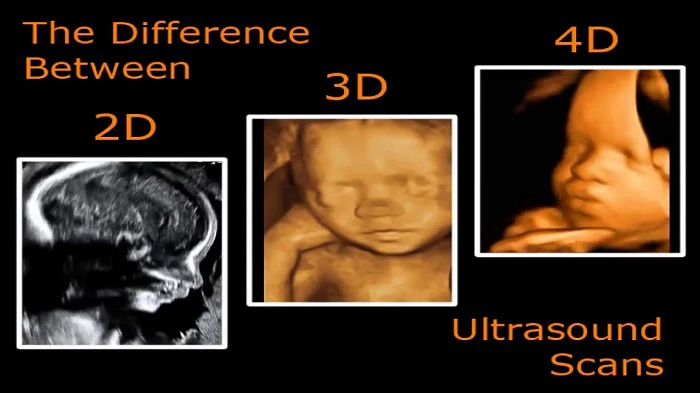

Siêu âm 4D là kết quả của công nghệ y học tiên tiến, nơi các thiết bị và phần mềm hiện đại được kết hợp để tạo ra hình ảnh sắc nét nhất của thai nhi. Khác biệt với siêu âm 2D và 3D, siêu âm 4D không chỉ là hình ảnh tĩnh mà là video động, giúp bác sĩ và phụ huynh quan sát chuyển động của thai nhi một cách rõ ràng và sống động.

Siêu âm 4D khác gì so với siêu âm 2D và 3D?

Siêu âm 4D cung cấp hình ảnh động và sắc nét về thai nhi, giúp quan sát chuyển động rõ ràng hơn, trong khi 2D và 3D chỉ cung cấp hình ảnh tĩnh với độ chi tiết thấp hơn. -